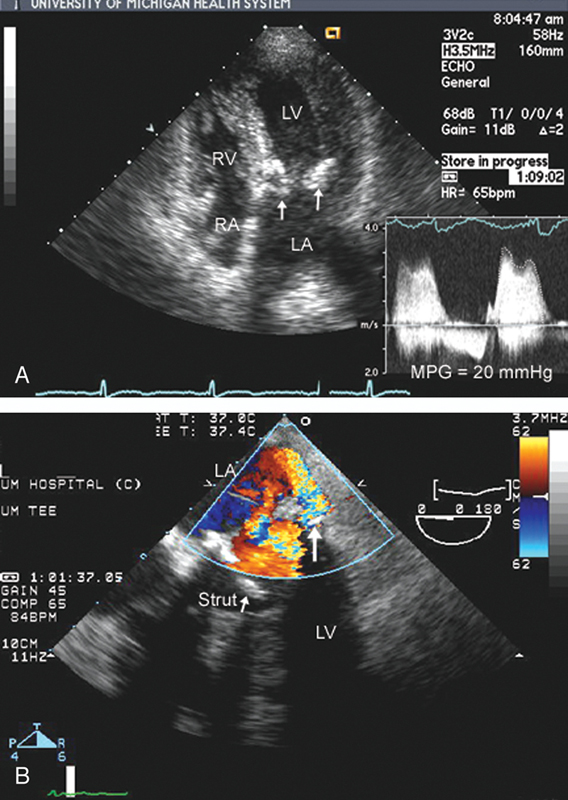

فحوصات تشخيصية لبعض امراض القلب والشرايين التاجية